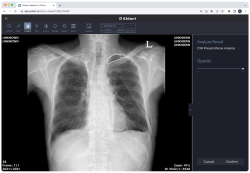

Promedius Inc. brings cutting-edge medical imaging AI cloud platform, AIdant to GITEX AFRICA 2023 (3)

(Source: GITEX Africa

2 years ago)